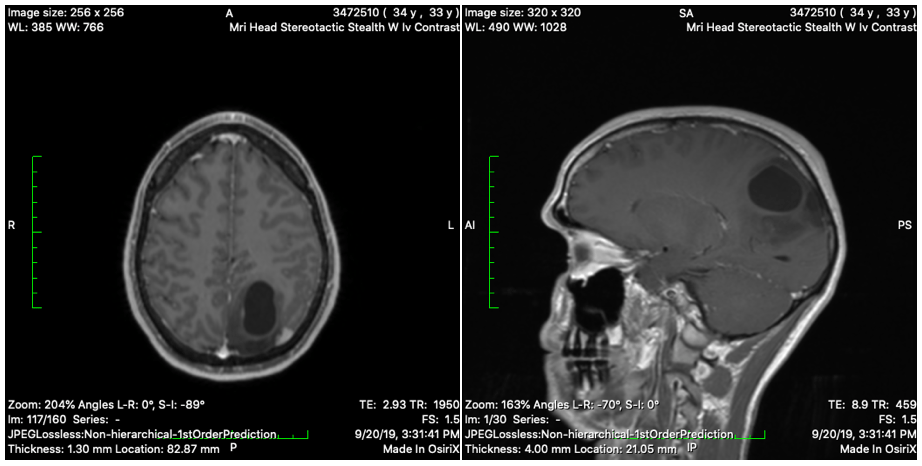

We decided to start this Caring Bridge site to share some news we found out about Brad. Friday September 6, we went into the ER due to a bad headache and vomiting. (We thought this was due to a concussion from wake boarding a few weeks ago). Brad had a CT scan done and it showed no trama that would be related to a concussion, but an abnormality. He then had an MRI done, and it showed a 4cm mass located towards the back left side of his brain. They do believe it to be cancerous, but a “better” more treatable type.

Please say a special prayer for protection for his vision. Looking at his most recent MRI they feel pretty certain he may have vision issues after surgery.